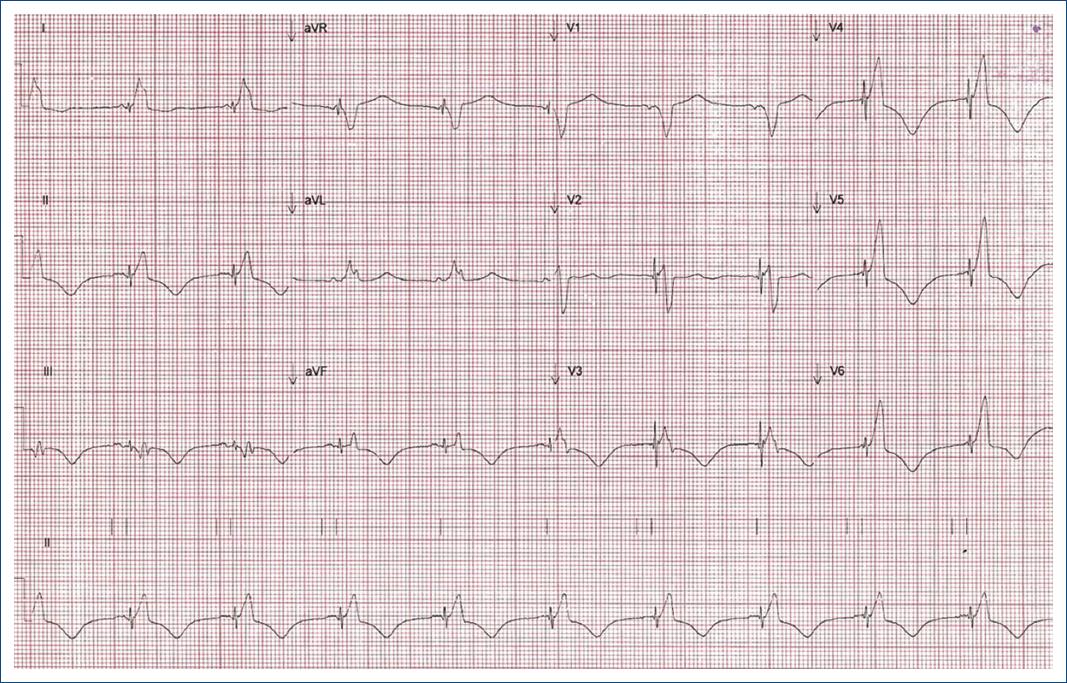

Posterior a 24 horas del procedimiento, se obtuvo ECG con reducción en la duración del QRS (Fig. 2). Se realizó una evaluación ecocardiográfica antes y después de la TRC mediante la técnica de rastreo de puntos (speckle tracking) sin estimulación se observó retraso en la conducción de las paredes anterior y posterior respecto a la pared septal, esto se explica por el BFA (Fig. 3). Posterior a la estimulación hubo mejoría significativa de la asincronía interventricular e intraventricular y la cuantificación de FEVI 3D final con software Syngo en Siemens Accuson S2000 fue del 36.6% (Fig. 4).

Figura 2 Electrocardiograma posterior a la estimulación hisiana. Intervalo R-R 929 ms, duración del QRS 160 ms, QT 525 ms, bloqueo de rama izquierda del haz de His.